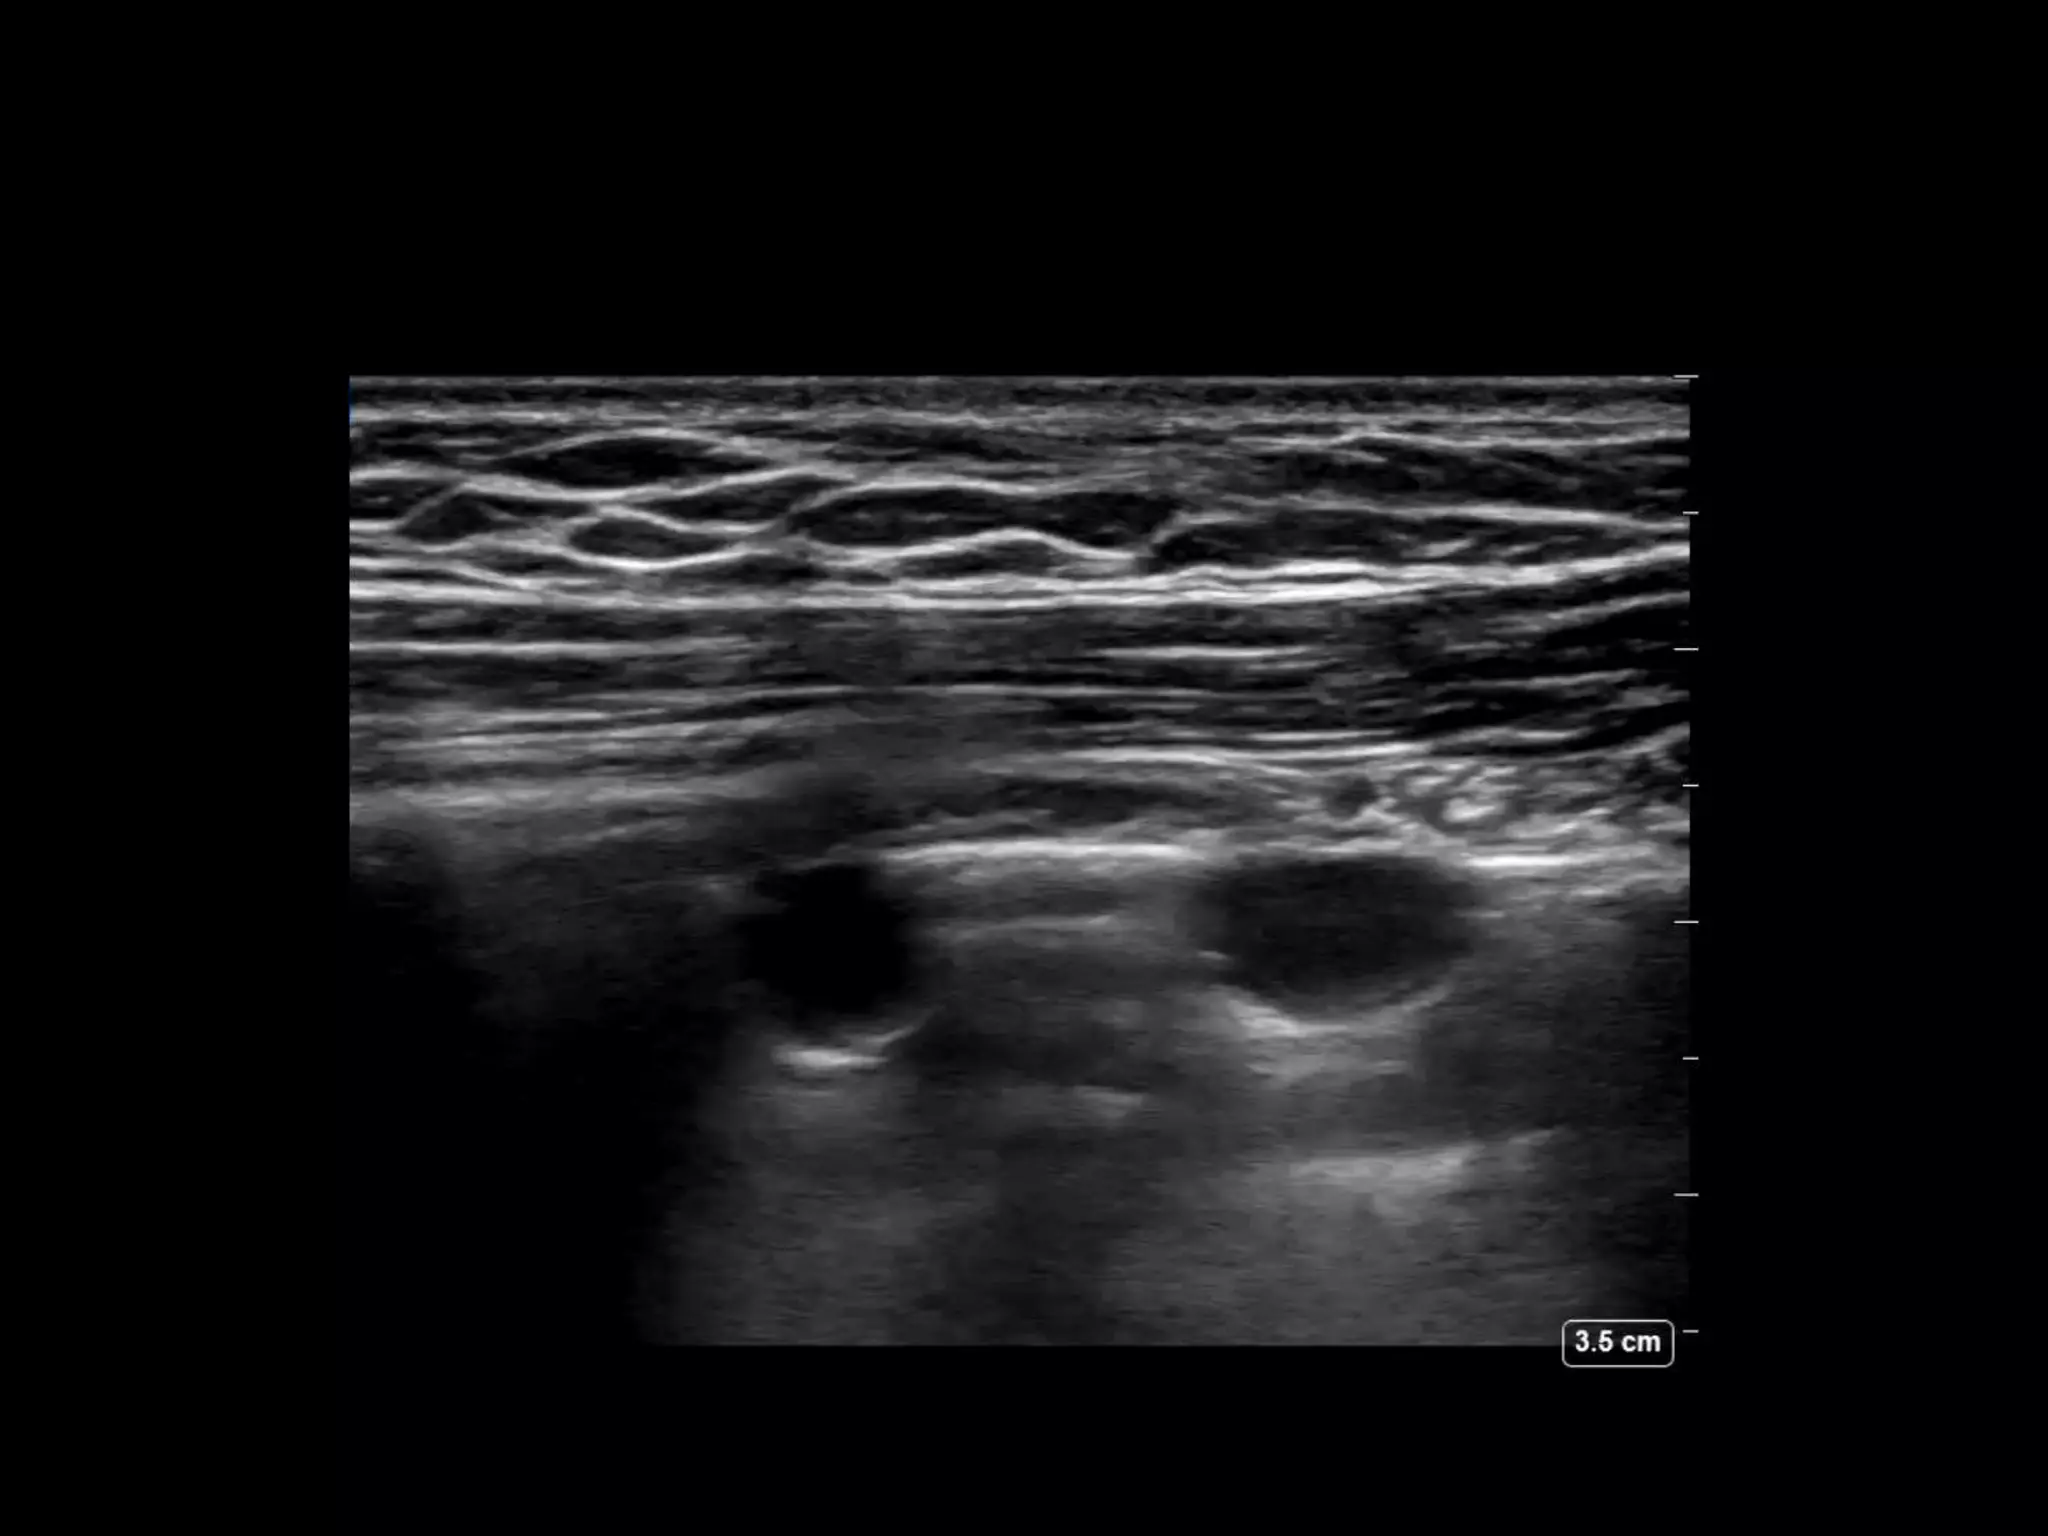

Pleural effusion

Size, anechoic or echogenic, loculated, solid nodules,

pleural thickening, compressive atelectasis